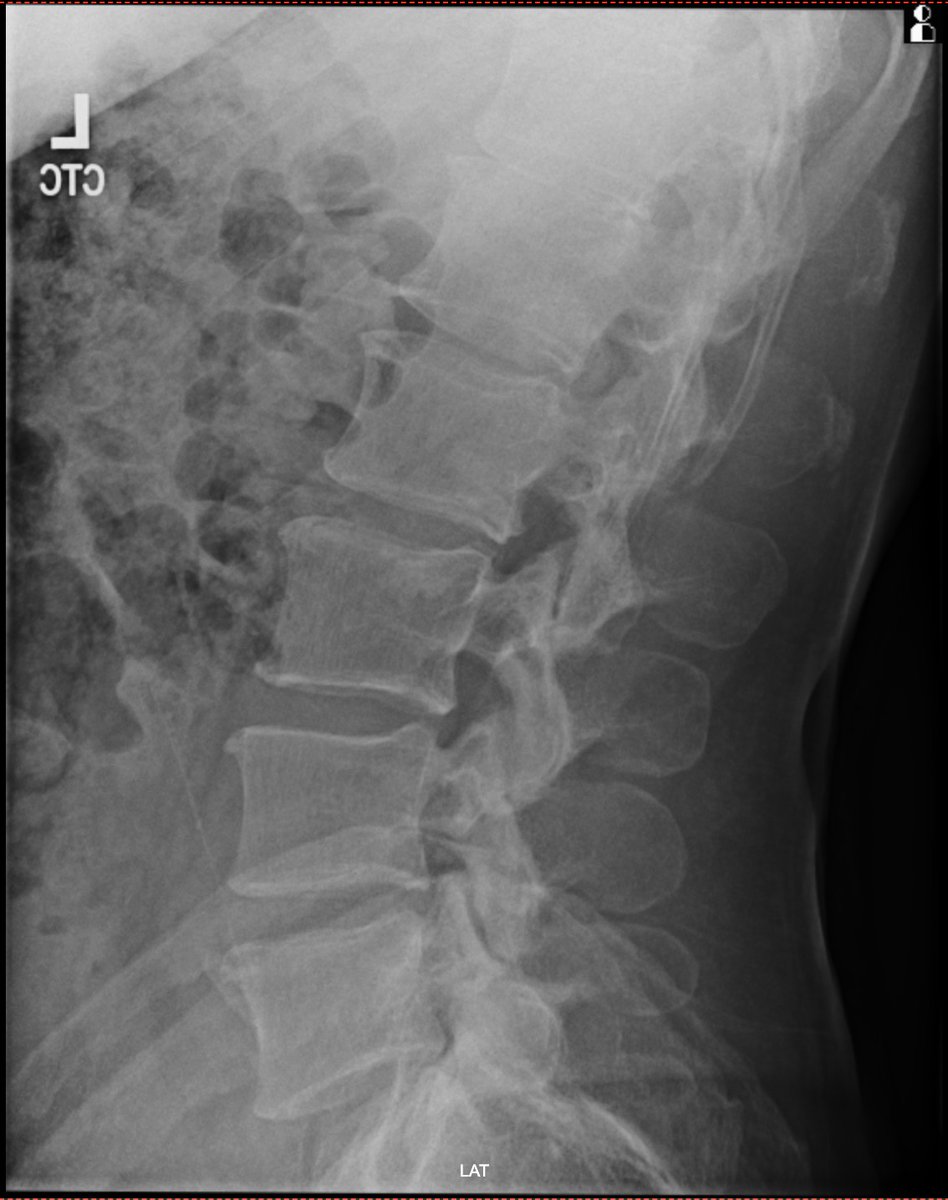

No differences in prevalences of pubic-related radiographic findings between football players with and without groin pain! Great to see another online paper from my PhD🤩 It is open access! 🆓 ⬇️ onlinelibrary.wiley.com/journal/160008… @SORC_C